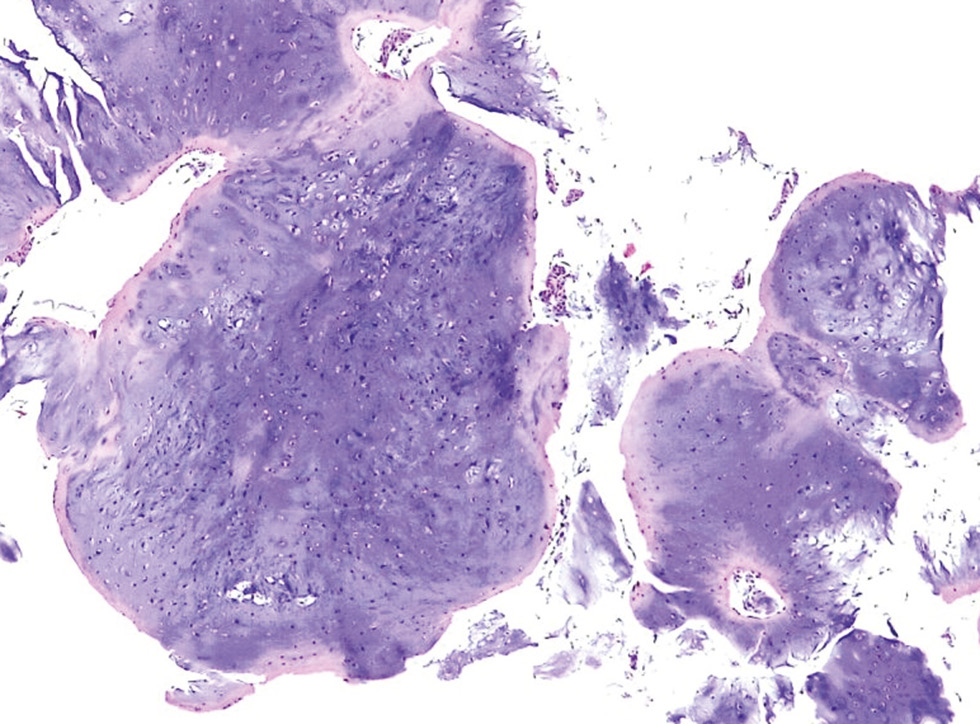

При гистологическом исследовании опухоль может иметь мультицентрическое дольчатое строение, с расположением долек в костномозговой полости и отдельно от главного очага поражения, без признаков деструкции в самих дольках. Дольки хряща представлены группами зрелых хондроцитов, расположенных в лакунах и разделенных солидным гиалиновым хрящевым матриксом, с умеренным количеством миксоидных изменений. Клетки опухоли преимущественно распределены дискретно, но могут выявлять и гиперклеточные участки [6, 38]. Для энхондром мелких костей свойственна многоклеточность. При этом клетки одинаковые, округлой формы, с плотными крупными ядрами правильной формы, с небольшим количеством митотических фигур [13, 39]. Часто встречаются двуядерные хондроциты. Возможно выявление участков деструкции кортикального слоя, отсутствие признаков инвазии опухоли в костномозговую полость и межтрабекулярные пространства предсуществующей кости (рис. 2) [40, 41].

Рис. 2. Энхондрома. Дольки гиалинового хряща с тонкой оболочкой из фиброзной ткани, окружающей дольки. Окрашивание гематоксилином и эозином, увеличение ×50. © Academy of Medical Sciences, Romanian Academy Publishing House, Bucharest, 2022. Распространяется на условиях лицензии CC BY-NC-SA 4.0. Источник: заимствовано из [DOI: 10.47162/RJME.63.4.04].